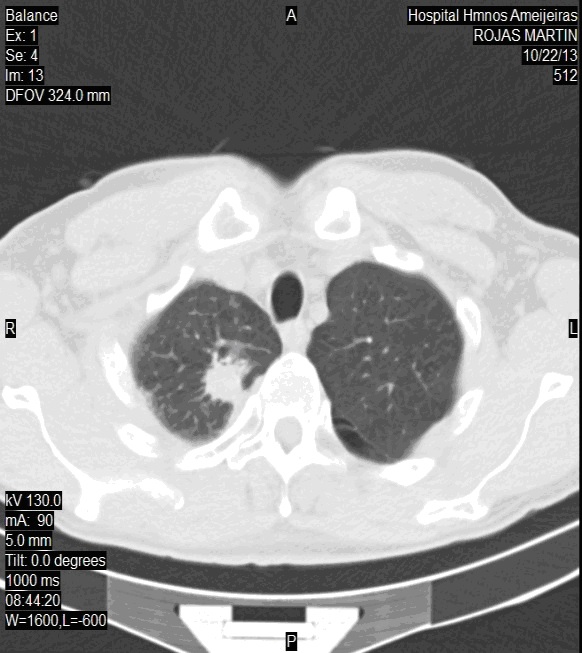

TAC de tórax, 7 de noviembre de 2012: nódulo tumoral lóbulo superior derecho, que mide 3,2 cm de diámetro. Se indican TAC endovenosa, se corrobora lesión tumoral, de borde irregulares y cavitada de 4,6x 3,7 cm. Adenopatías subcarinales que miden 109 x 19 mm.

Resonancia magnética nuclear (RNM) de cráneo, 20 de noviembre de 2012: existen dos lesiones expansivas, una región fronto-parietal que mide 16 x 17 mm, rodeada de edema que no muestra efecto de masa, la otra ubicada hacia el cerebelo hemisferio izquierdo que mide 19 x 17 mm con edema (imagen 1).

IMAGEN 1. RNM de cráneo: 20 de noviembre de 2012